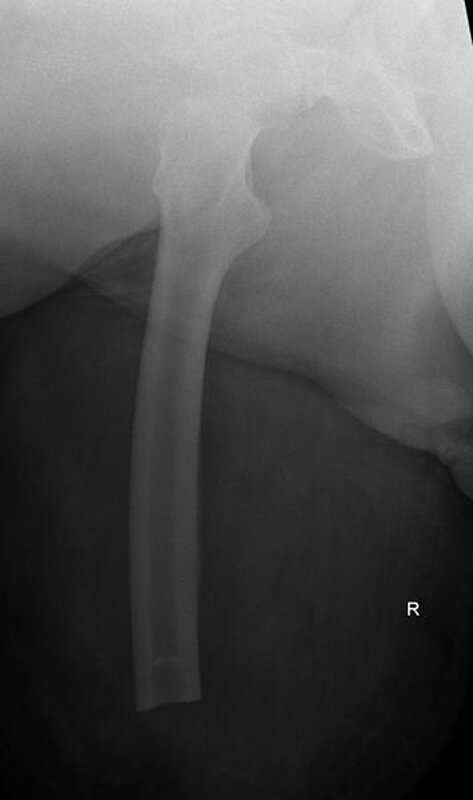

Im weiteren Verlauf zeigten sich die Weichteile des rechten Unterschenkels zunehmend mazeriert und belegt. Zudem sei der Patient erneut gestürzt. Eine erneut durchgeführte Röntgendiagnostik zeigte erneut eine periprothetische Tibiafraktur (Abbildung 3) bei einliegender achsgeführter KTP mit langem tibialem Stem und bekanntem periprothetischem Infekt mit Candida parapsilosis. Wir haben die Befunde ausführlich mit dem Patienten besprochen und in Zusammenschau der Befunde schließlich die Indikation zur Oberschenkelamputation gestellt.

Diese konnte komplikationslos im Mai 2018 durchgeführt werden (Abbildung 4 und 5).

Womöglich hätte der drastische Schritt einer Amputation durch eine frühzeitige Prothesensanierung, welche jedoch durch den Patienten abgelehnt wurde, verhindert werden können.